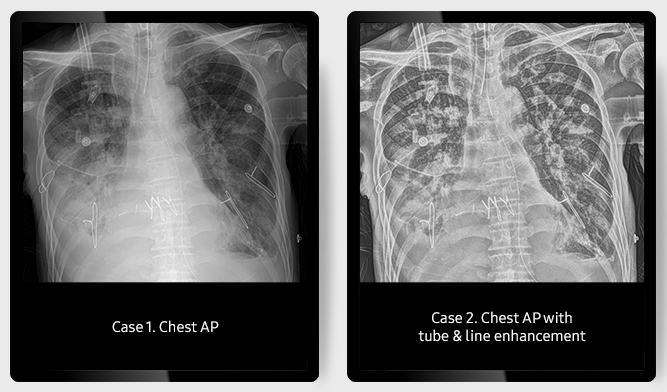

Функция повышения четкости легочного рисунка TLE

Функция Tube & Line Enhancment улучшает четкость изображений легких с помощью одного клика на экране.